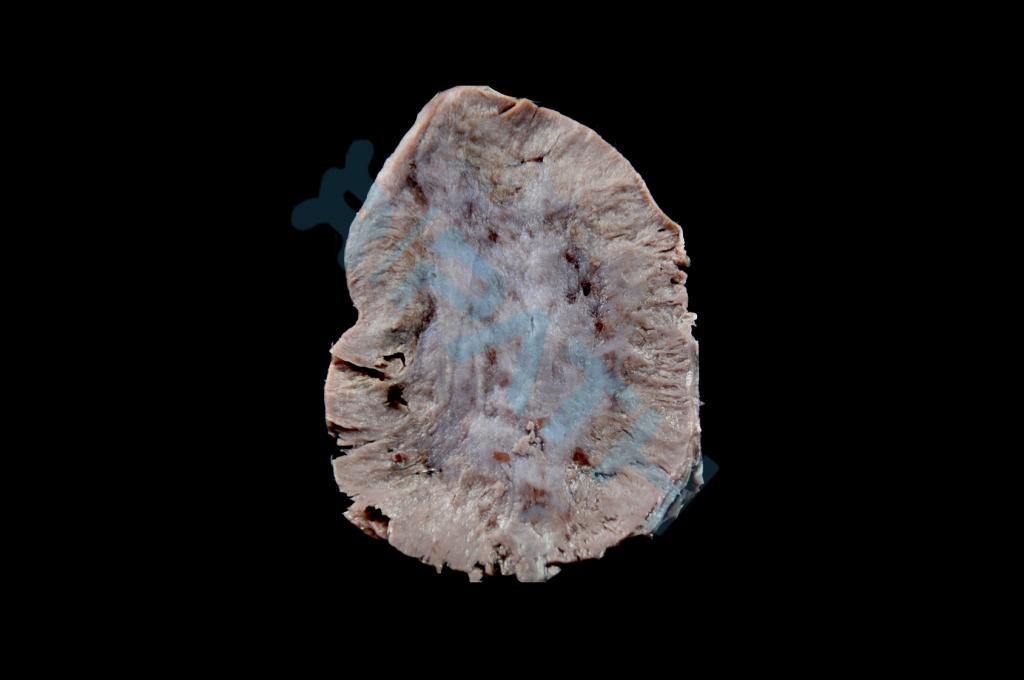

肾上腺皮质腺瘤